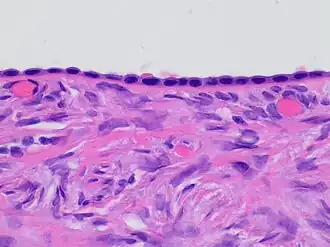

Histology of ovarian surface epithelium. H&E stain. The epithelium is the chain-like covering with round dark blue nuclei at top.

The ovarian surface epithelium, also called the germinal epithelium of Waldeyer,[1] or coelomic epithelium, is a layer of simple squamous-to-cuboidal epithelial cells covering the ovary.[2]